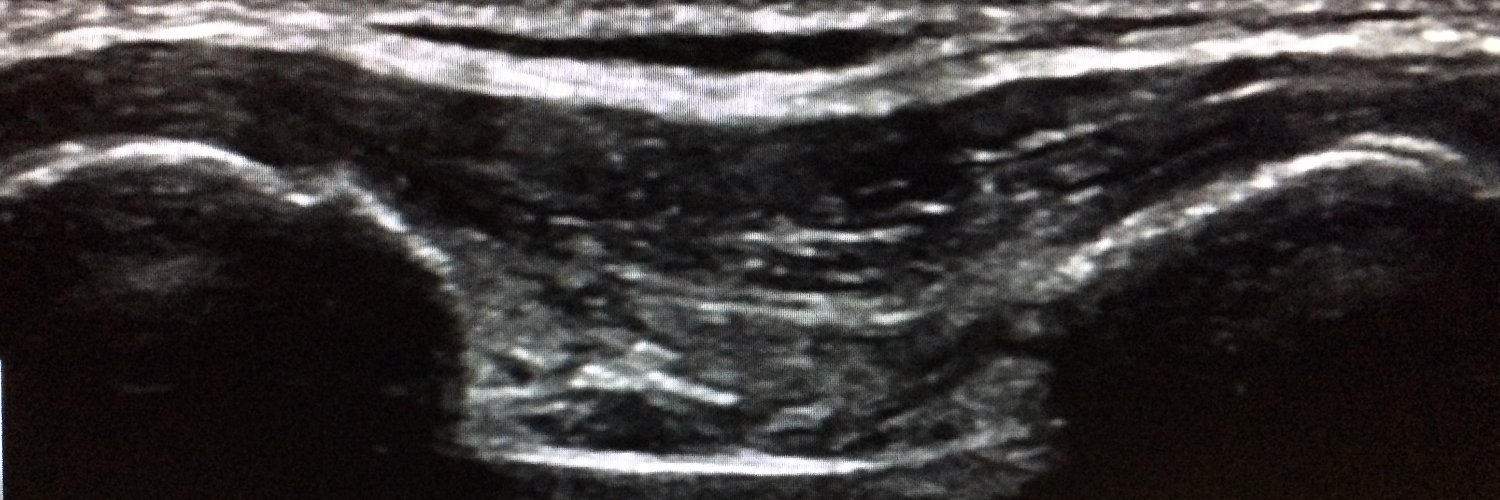

Intussusception reduction may not require completion emergently (within 2 hours after diagnosis), but potentially may be safely performed on an urgent basis (within 8 hours)! @AJR_Radiology @TCHRadiology @MarlaSammer ajronline.org/doi/10.2214/AJ…